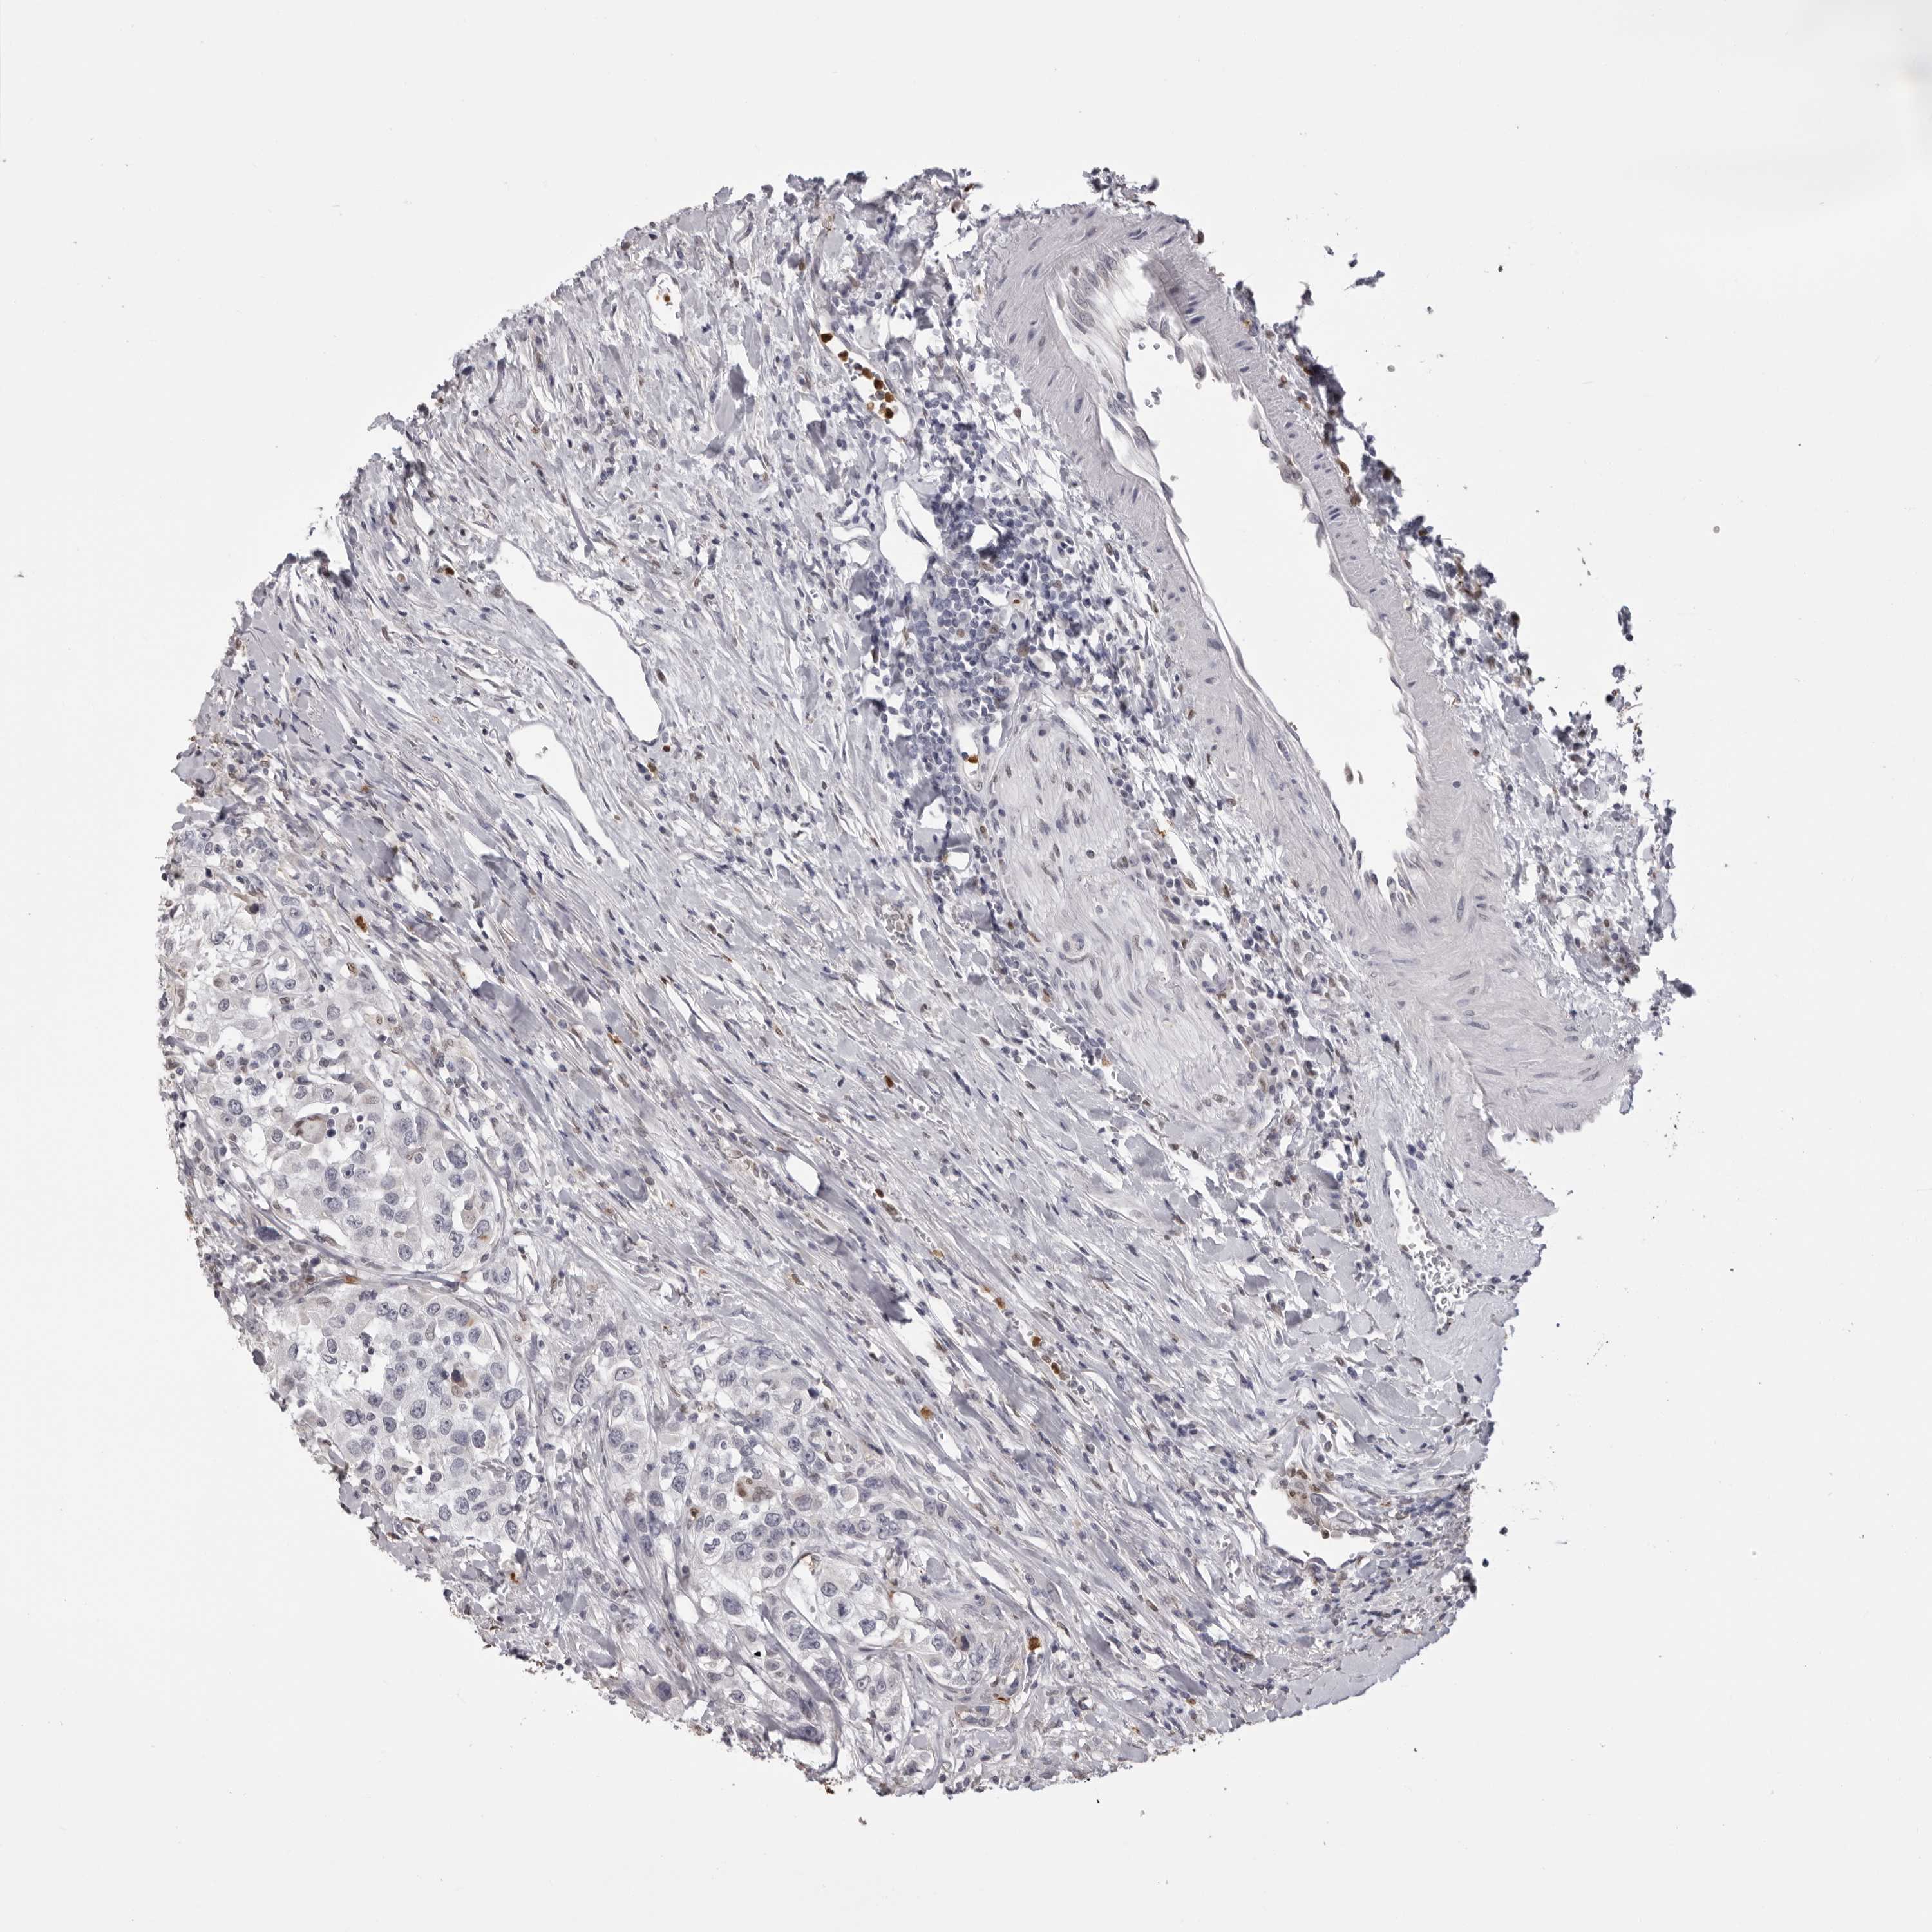

UROTHELIAL CANCER - Protein expressioni

A mouse-over function shows sample information and annotation data. Click on an image to view it in a full screen mode. Samples can be filtered based on level of antibody staining by selecting one or several of the following categories: high, medium, low and not detected. The assay and annotation is described here.

Note that samples used for immunohistochemistry by the Human Protein Atlas do not correspond to samples in the TCGA dataset.

Antibody stainingi

Antibody staining in the annotated cell types in the current human tissue is reported as not detected, low, medium, or high, based on conventional immunohistochemistry profiling in selected tissues. This score is based on the combination of the staining intensity and fraction of stained cells.

Each image is clickable and will lead to virtual microscopy that enables deeper exploration of all samples and also displays staining intensity scores, fraction scores and subcellular localization as well as patient and tissue information for each sample.

Antibody CAB025657

Staining

High

Medium

Low

Not detected

Intensity

Strong

Moderate

Weak

Negative

Quantity

>75%

75%-25%

<25%

None

Location

Nuclear

Cytoplasmic/membranous

Cytoplasmic/membranous,nuclear

Urothelial carcinoma, Low grade

Urothelial carcinoma, High grade